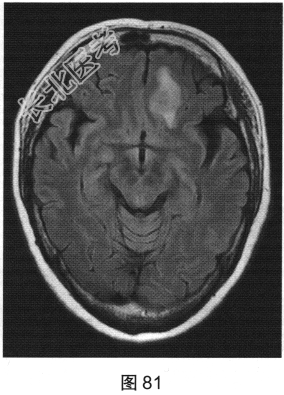

- 多项选择题2.[提示]患者行MRI检查,如图80~图85所示。患者MRI检查的阳性影像学表现包括( )

A、MRI示右侧大片水肿

B、病变增强扫描未见明显强化

C、MRI示左侧大片水肿

D、FLAIR呈稍高信号

E、病变增强扫描可见明显强化

G、MRI示左侧异常信号影

H、MRI示右侧异常信号影